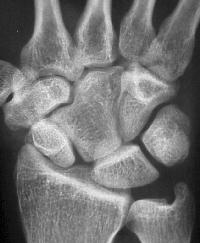

The scapholunate angle is abnormal, about 80 degrees.

Radial and ulnar deviation views show minimal additional scapholunate widening in ulnar deviation.